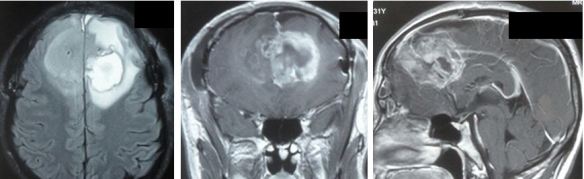

Brain Cancer: Operation, Radiation, Blind After Two Weeks

Amar (not real name) is a 32-year-old Indonesia male. In April 2016, he had a seizure and vomited. He was immediately sent to the hospital in Batam. After performing an X-ray, he was given some medication and sent home. He was able to go back work.

One week later, Amar went into a coma and was sent back to the hospital again. The doctor told the family Amar had stage 4 brain cancer. He was asked to immediately undergo a brain surgery. The doctor said that was the only option left. The risk of surgery would be: Amar could suffer memory loss or he could go blind.

The operation was carried out in Batam and Amar regained consciousness. The operation cost IDR 170 million. Unfortunately the surgeon was only able to remove 70 percent of the tumour. Amar was asked to undergo chemotherapy which the family rejected.

This is what Amar’s brain looked like after the surgery.

brain-augus-batam

Amar was brought to consult two doctors in Johor Baru. One surgeon suggested that Amar should undergo another surgery to removed more of the tumour in his brain. An oncologist suggested radiotherapy. The family opted for the latter and he had 30 sessions of radiation. Radiotherapy cost the family RM 12,000.

Two week after the completion of the radiation treatment, Amar became blind. As a follow up the oncologist put Amar on oral chemotherapy. Amar had three round of chemotherapy. Then his brother decided to come to Penang to seek our help.